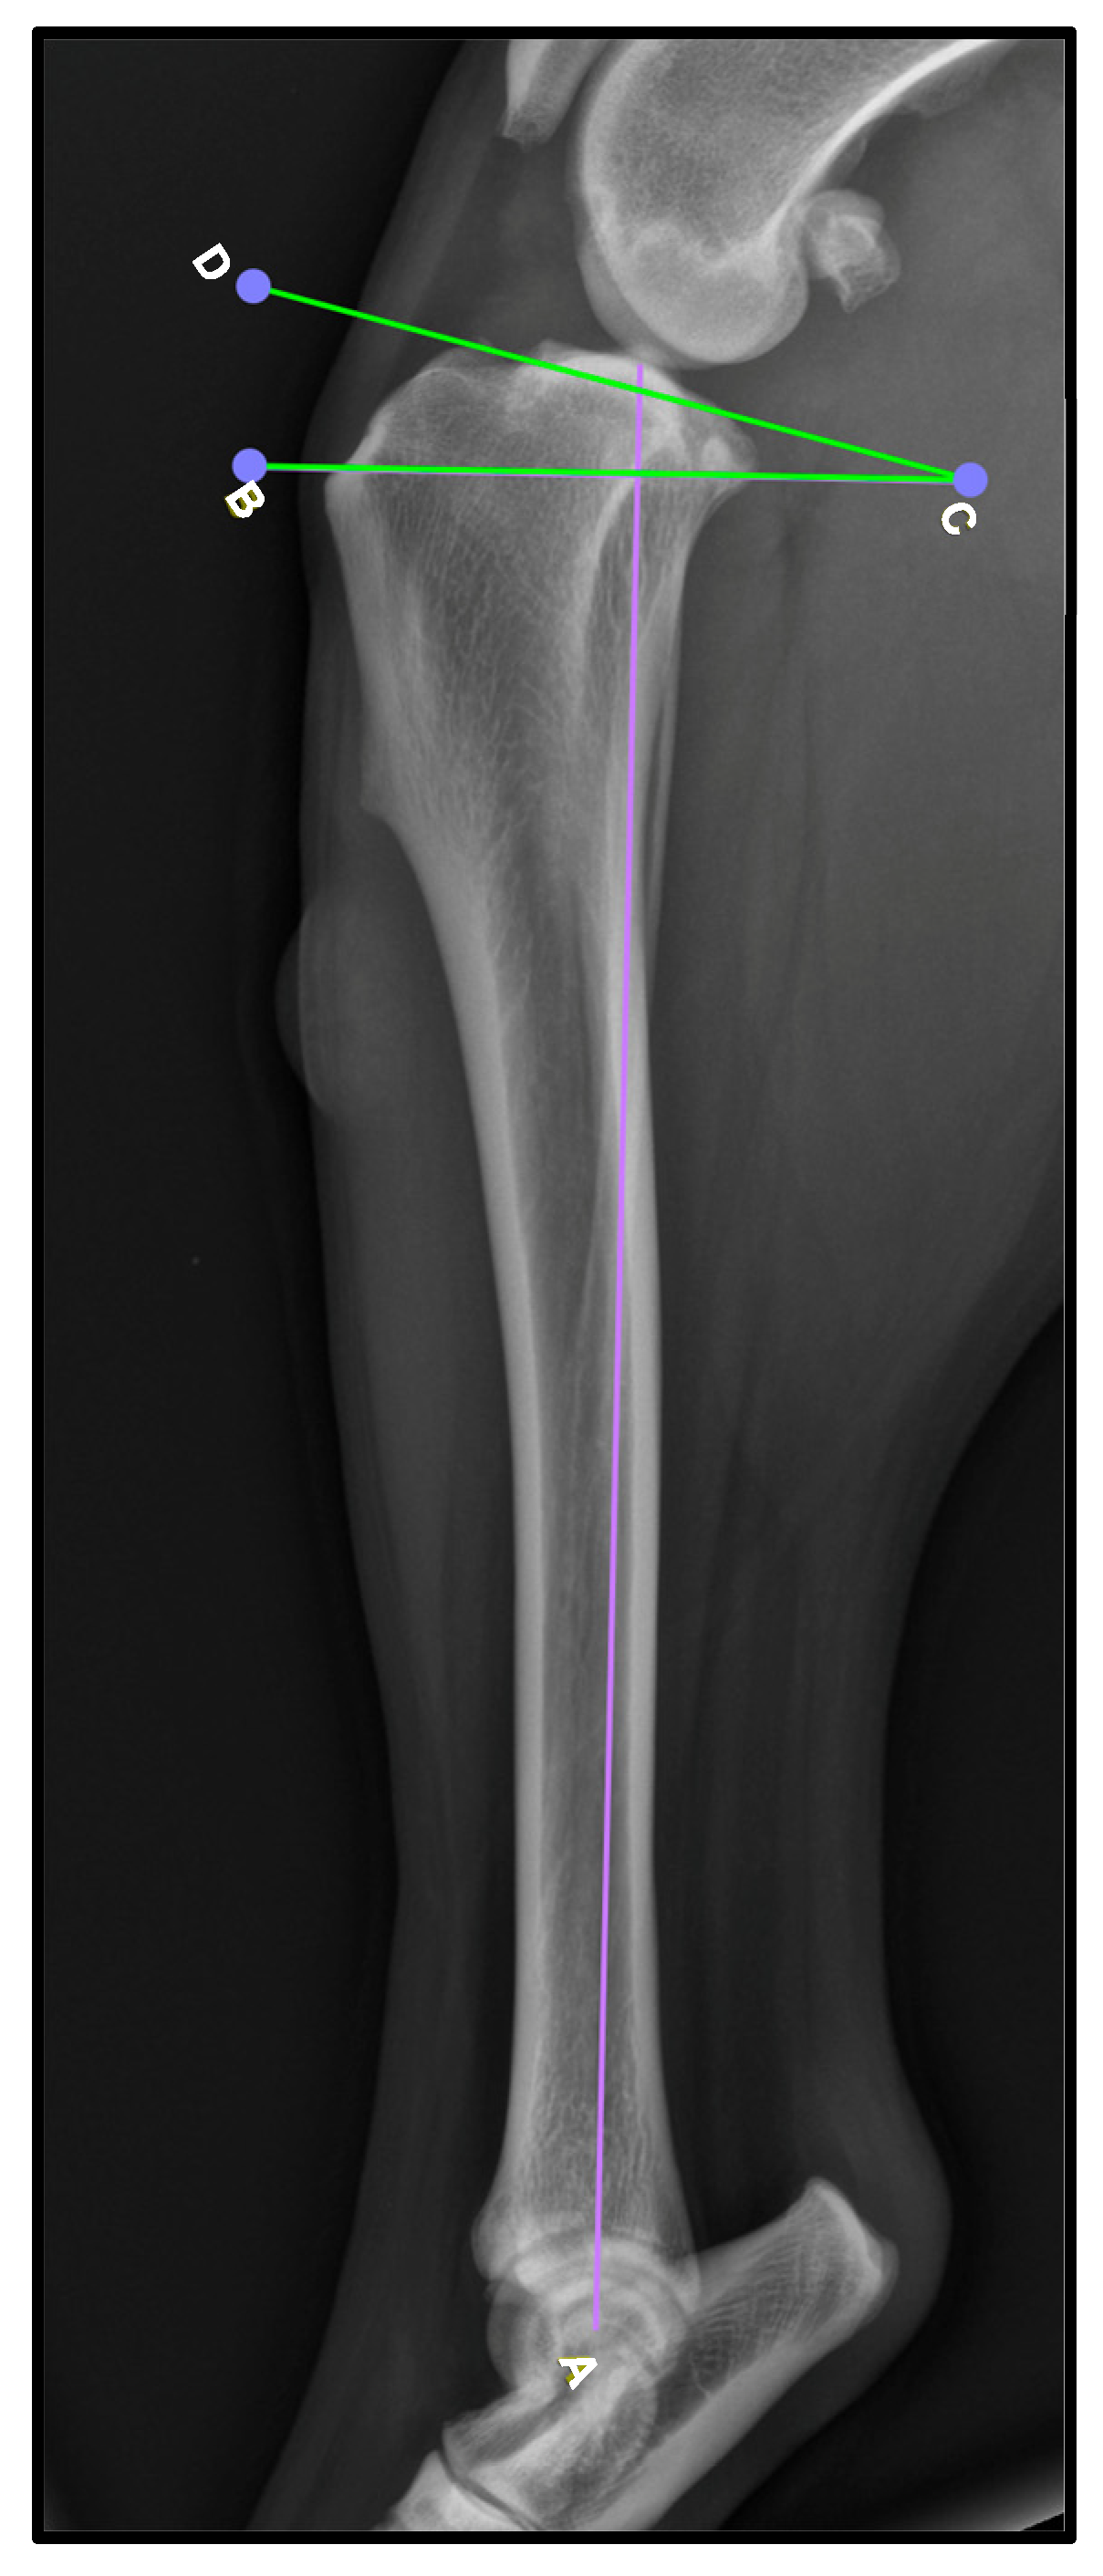

To determine the thickness of the patellar ligament (Figure 2), we followed the method previously described by DeSandre-Robison et al. (2017) [14]. To standardize measurements across patients, the total length of the patellar ligament was first measured from its proximal insertion at the patella to its distal insertion at the tibial tuberosity. This total length was then divided into four equal segments. The ligament thickness was measured at the three junction points between these segments, ensuring that reference points were proportional to ligament length in each patient. Taking this into account, three points were measured in every patient: one proximal, one distal, and one in the middle of the ligament.

Figure 2.

Lateral knee radiographic view (LL) illustrating the measurement of patellar ligament thickness. The ligament was divided into four equal segments, and thickness was recorded at three predefined reference points: proximal (P), middle (M), and distal (D). These measurement locations are marked in green for clarity.